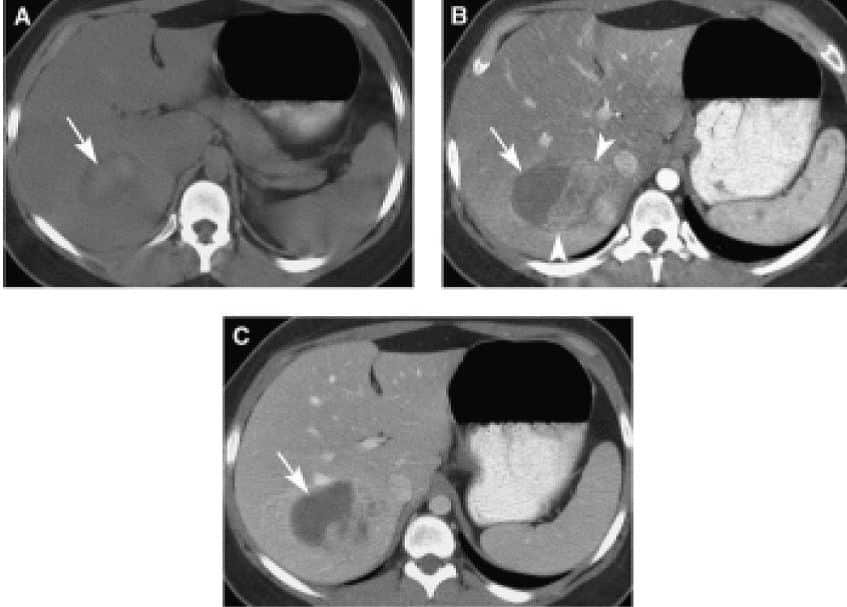

Mujer de 25 años con un adenoma hepático demostrado por biopsia. La imagen precontraste (A) muestra una región hiperdensa de hemorragia. La imagen de la fase arterial inicial (B) muestra regiones de realce rápido. La región de la hemorragia muestra la ausencia de realce en las fases arterial inicial y venosa portal (C).